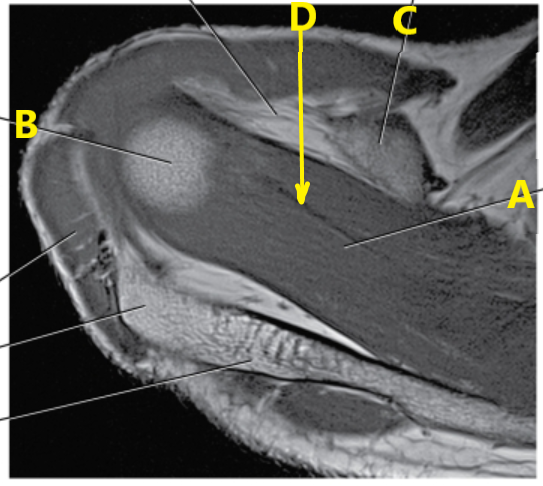

What is letter c ?

Superior glenoid labrum

What is letter A?

Brachial artery

What is letter B pointing to ?

Humerus

What is letter C pointing to ?

Coracoid process

What is letter A pointing to ?

Supraspinatus muscle

Subscapularis tendon